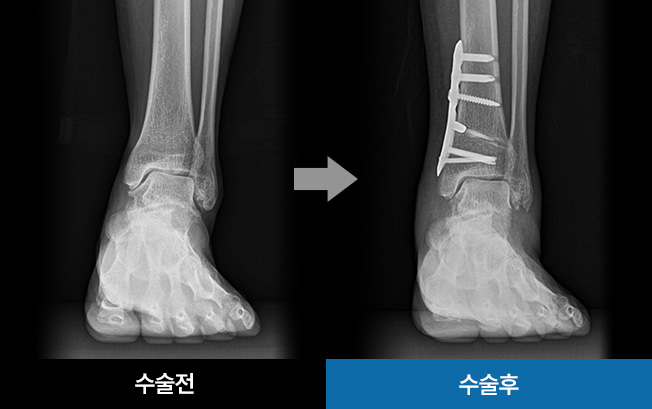

수술 전 / 수술 후

• 수술적치료 MICA수술

2mm정도의 미세 절개를 통해 주변 조직을 손상시키지 않고

뼈를 절골해 휘어진 발가락을 교정하는 수술

• 발목교정술

(SMO)

이 수술은 틀어진 발목을 바로잡아 통증을 감소시키고

관절의 부담을 덜어주는 것을 목표로 합니다.

발목 연골 한쪽만 닳아 발생하는 발의 기울어짐을 교정하고,

손상된 연골 부위의 압력을 줄여주기 위해 체중이 정상적인

연골 부위로 분산되도록 축을 이동시키는 수술법입니다.